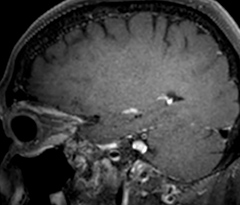

Fast acute stroke protocol

This is an example of acute ischemic stroke with distal occlusion of the right posterior cerebral artery. Note the improved visibility of the ischemic territory on the diffusion weighted image with high b-value. The 3D FLAIR shows a distal PCA occlusion. The fast SWIp depicts the thrombus on the isolated second echo image. The total scan time (including SmartBrain, preparations and a fast 3D T1w TSE Gd) is 8:00 minutes.

Fast acute stroke protocol A

Fast acute stroke protocol B